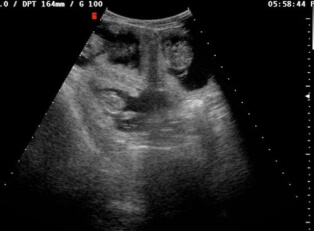

Ультразвуковое исследование для домашних животных является современным и информативным методом диагностики разных органов. Данные такой процедуры позволяют точно оценить состояние внутренних органов домашнего питомца и определить точный диагноз.

При этом ультразвуковая диагностика не несет опасности для здоровья четвероногого друга. С помощью УЗИ ветеринар может исследовать органы брюшной полости, грудной полости, оценить состояние, выбрать тактику лечения, выявить новообразование или инородное тело, определить его размеры и точную локализацию.

С помощью ультразвукового сканирования брюшной полости можно увидеть размеры и положение внутренних органов, оценить плотность тканей и их структуру, визуализировать наличие свободной жидкости.

Сделать УЗИ собаке несложно. Процедура не требует особой подготовки. Животное укладывают на спину или бок на столе или специальной подушке. Если питомец нервничает, ему заранее вводят седативный препарат. Владелец находится рядом и во время УЗИ при необходимости помогает врачу, фиксируя лапы собаки. На кожу наносится специальный гель, и с помощью датчика специалист изучает необходимый орган. Процедура занимает до 20 минут. В результате исследования ветврач ставит диагноз.